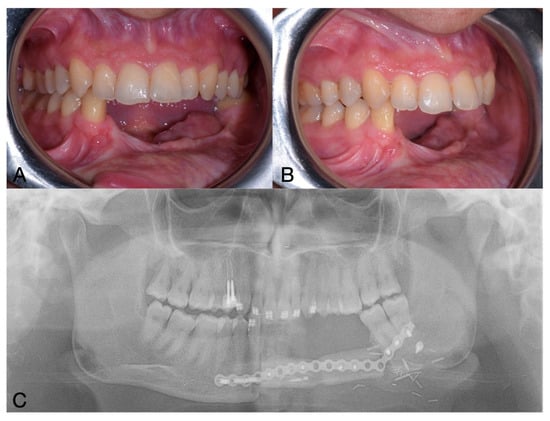

2. Case Report